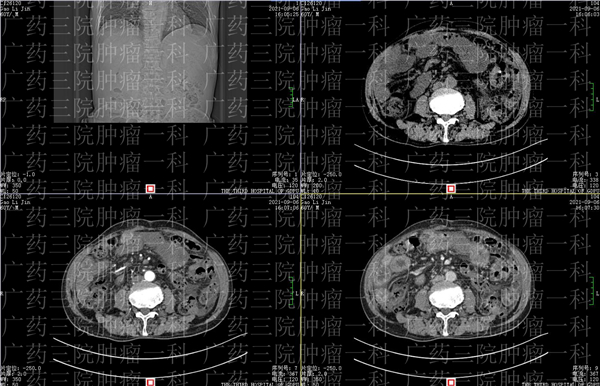

正常情況下,人體的腹腔都有少量積液,對腸道蠕動起潤滑作用,但癌症患者不同,腹腔內的液體量增加形成了腹水,就成了一種病症。廣東的高先生在淋巴瘤化療後,就出現了腹水,為了進一步治療,來到了廣藥三院腫瘤一科。

惡性腹水是晚期腫瘤患者常見的併發症之一,發生率為15%-50%,高先生在三次化療後,就出現了腹脹、食慾下降的後遺症。在治療無明顯好轉的情況下,高先生來到了廣東藥科大學附屬第三醫院尋求微創治療。

醫生為高先生會診後,給予了微創灌注栓塞治療+免疫治療的綜合治理方案。經灌注栓塞術後,高先生病情有所好轉。